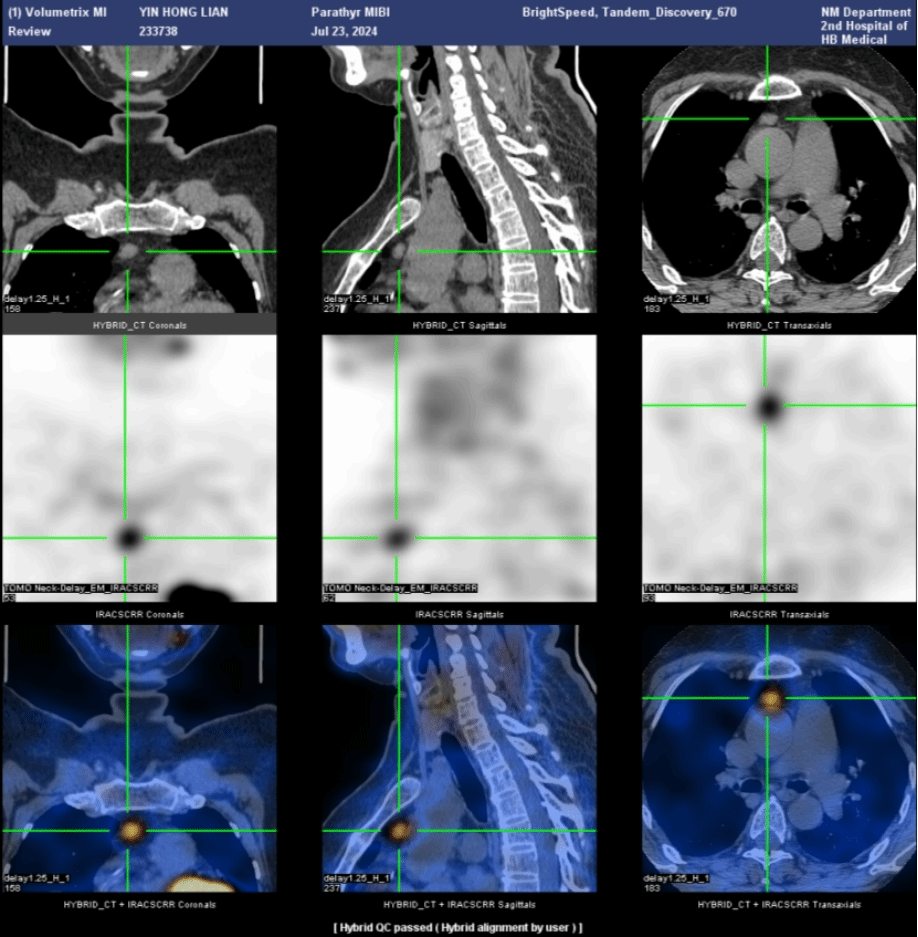

进一步的SPECT/CT断层融合显像(图6)显示,左上甲状旁腺形态增大,呈长条形,大小约1.3cm×0.6cm×4.5cm,并伴显像剂异常浓聚,考虑为功能亢进的甲状旁腺病变,首先考虑腺瘤。

后来段阿姨进行了手术治疗,病理为甲状旁腺腺瘤,术后段阿姨的血清钙恢复正常,PTH降低。